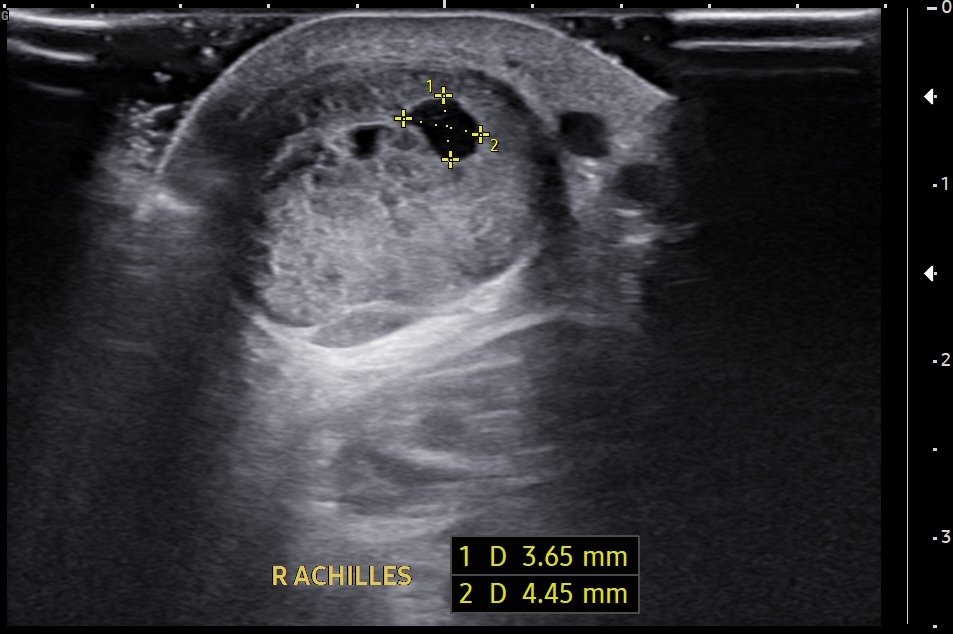

Short-axis ultrasound image of the midportion Achilles tendon showing the depth and width of the largest intrasubstance partial tear.

Short-axis ultrasound image of the midportion Achilles tendon showing the tendon thickness measurement.